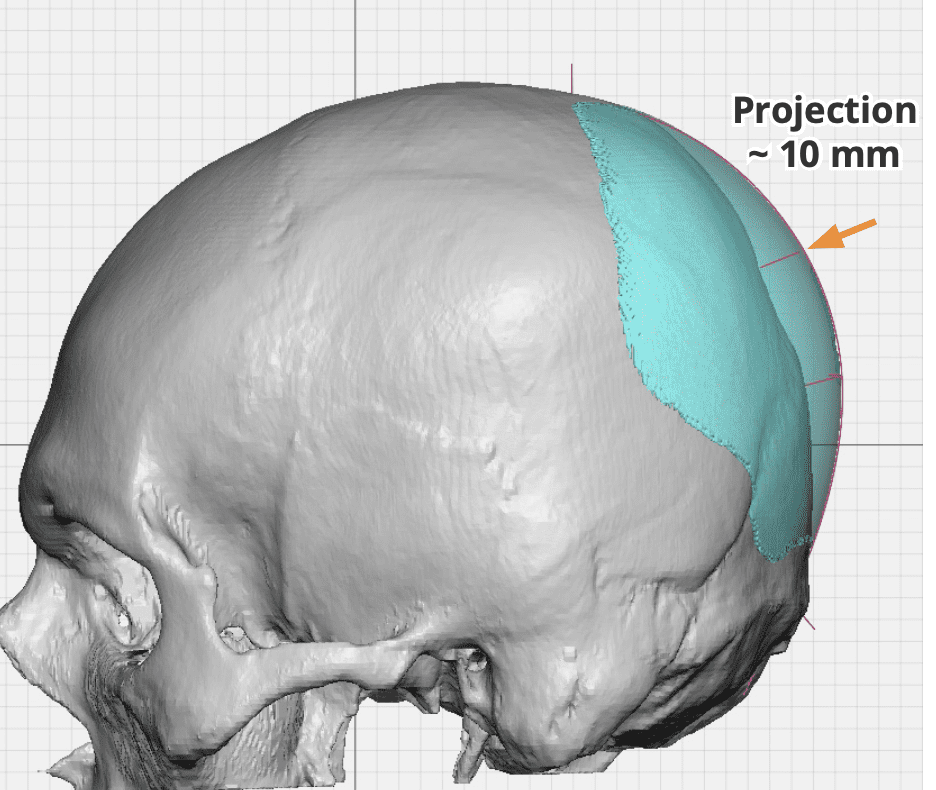

Desire for increased projection of flat back of head.

Placement of a custom skull implant to increase the projection of the back of the head by 15mms and 120ccs of volume.

Desire for increased projection of flat back of head.

Placement of a custom skull implant to increase the projection of the back of the head by 15mms and 120ccs of volume.